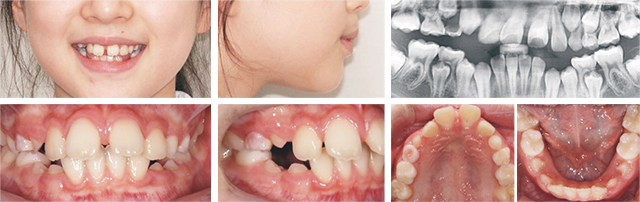

위턱의 성장이 부족하고 아래턱 성장이 과도하여 치아가 반대로 물리는 초등학생 환자입니다. 이 상태가 지속되면 성장이 끝나도 앞니가 반대로 물리게 되어, 저작, 발음, 외모에 영향을 주기 때문에 조기 치료가 중요합니다. 고운미소에서는 골격 부조화를 개선시키기 위해 페이스마스크를 이용한 교정을 진행하였습니다.

페이스 마스크를 하루에 7시간 이상 착용하였고, 위턱은 전방으로, 아래턱은 성장 방향에 따라 후방 이동되었습니다. 아래턱의 경우 키 성장이 일어나는 동안 지속적으로 성장하기 때문에 정기적으로 체크하여 재발 여부를 지속적으로 관찰하는 것이 중요합니다.